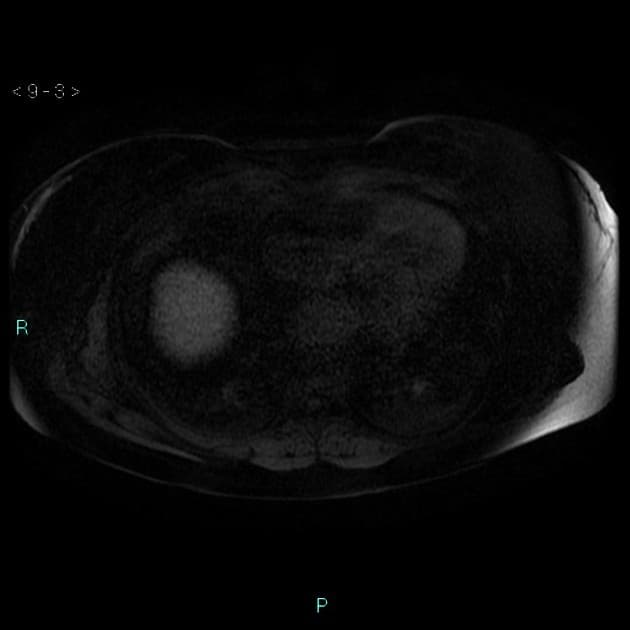

- Tổn thương này tăng tín hiệu (hyperintense) trên hình ảnh T2-weighted MRI.

- Trên hình ảnh cộng hưởng từ có tiêm thuốc tương phản động (dynamic contrast-enhanced imaging), thấy tăng quang dạng nốt (nodular) ở vùng ngoài viền (peripheral) ban đầu, tiếp theo là quá trình lấp đầy dần từ ngoài vào trong (slow centripetal filling).

- "U sợi mạch gan thường biểu hiện tăng tín hiệu T2 và tăng quang dạng nốt ở viền ngoài với quá trình lấp đầy từ từ từ ngoài vào trong trên cộng hưởng từ có tiêm thuốc tương phản động."

U sợi mạch gan là khối u gan lành tính phổ biến nhất, thường được phát hiện tình cờ trên hình ảnh học. Bệnh xuất phát từ các mạch máu bất thường và gồm các khoang giãn chứa đầy máu được lót bởi tế bào nội mô. Trên cộng hưởng từ (MRI), hình ảnh điển hình bao gồm tăng tín hiệu rõ rệt trên T2 và kiểu tăng quang dạng nốt ở vùng ngoại vi trong thì động mạch, tiếp theo là quá trình lấp đầy dần từ ngoài vào trong ở các thì muộn. Dấu ấn hình ảnh này rất đặc hiệu, cho phép chẩn đoán chắc chắn không xâm lấn trong hầu hết các trường hợp. Mặc dù có thể sinh thiết, nhưng thủ thuật này tiềm ẩn nguy cơ chảy máu và thường được tránh. Điều trị mang tính bảo tồn, không cần cắt bỏ hay theo dõi định kỳ trong các trường hợp điển hình, trừ khi có nghi ngờ chẩn đoán hoặc bệnh nhân có triệu chứng.